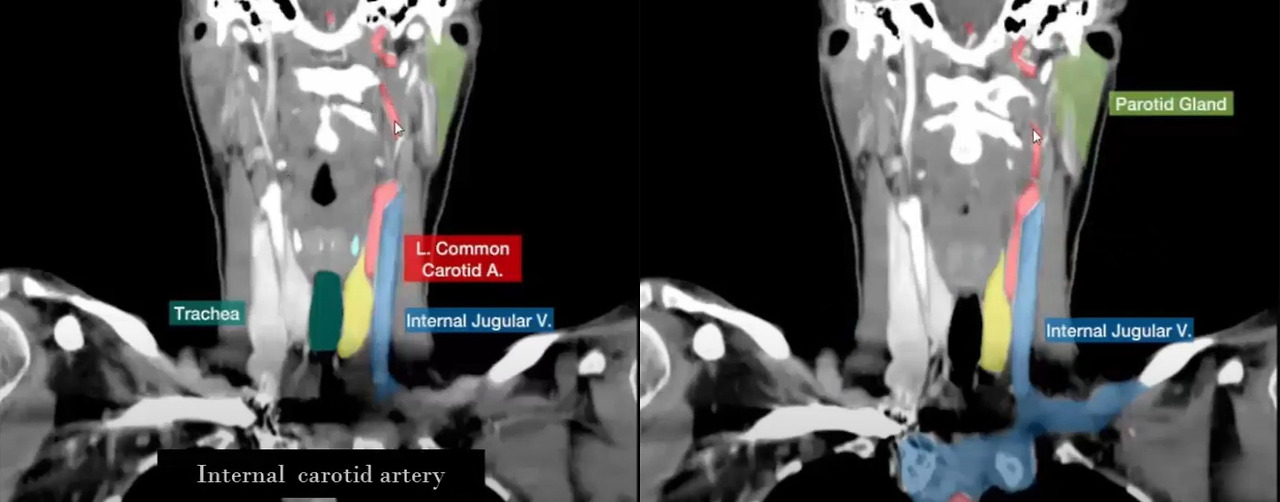

이러한 사항을 좀 더 다각적으로 살펴보기 위해서 유튜브에서 찾은 사람 목부위 CT 영상을 설명하는 동영상의 일부분을 캡처해 보았습니다.

유튜브 동영상 'CT scan of neck coronal and sagittal anatomy study'에서 관련 영상을 캡처해 보았습니다. (출처 : https://youtu.be/bnPPzLoaFwU?si=S6L4fhEms55inRNJ )

유튜브 영상에서도 정맥을 파란색, 동맥을 빨간색으로 알아보기 쉽게 칠해놓은 것을 볼 수 있는데...

가장 바깥쪽에 있는 혈관이 내경 정맥 (Internal Jugular V.)으로 표시되어 있는 것을 쉽게 알아볼 수 있습니다.